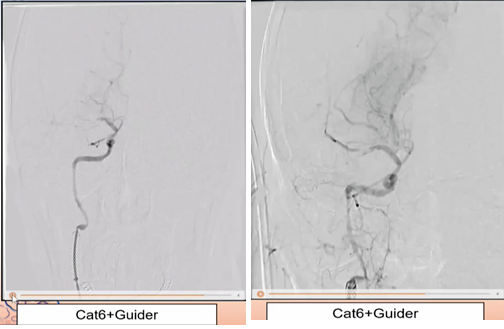

血管再通后造影

血管再通及左椎支架植入

左椎支架植入后造影